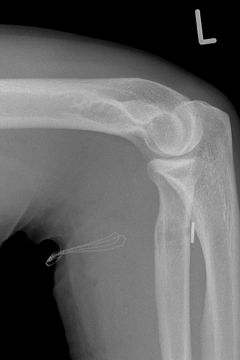

DISTALER ABRISS DER BIZEPSSEHNE

Der Bizepsmuskel zieht durch die Beugeseite des Ellenbogengelenkes und setzt auf einem Knochenvorsprung des Speichenknochens (Tuberositas radii) gelenknah am Unterarm an. Bei einem Abriss dieser Sehne fehlt die Kraft für die Umwendbewegung und Beugung des Ellenbogengelenkes.

Ziel der operativen Behandlung ist die Wiederanheftung des Muskels an der Tuberositas radii. Durch die Lage des Knochenvorsprunges tief im Ellenbogen und den sehr nahen Verlauf des Speichennervs (n. radialis) erfordert die operative Versorgung ein vorsichtiges Vorgehen.

Das Einheilen des Sehnensatzes muss nachfolgend geschützt werden, so dass ein Belastungsaufbau und die volle Streckung des Gelenkes erst schrittweise anschließend erarbeitet werden kann.

Bild Bizepssehnenrefixation

Bizepssehnenrefixation Röntgenbild